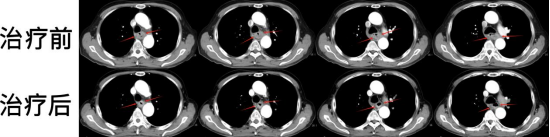

圖注:胸部CT掃描治療前后比對。上排為治療前,可見食管癌環(huán)周病灶,嚴(yán)重阻塞食管;下排為治療后,食管癌病灶縮退,食管形態(tài)基本恢復(fù)正常。